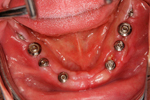

② 下あごにインプラント(人工歯根)を埋入しました。これで、まったく歯がなかったところに歯の土台が固定されました。

ここに、人工の歯を乗せしっかりと固定します。従来の入れ歯は歯がまったくない場合、歯肉に乗せるしかありませんでした。

③ 下あごの人工歯です。インプラントの上にキャップを入れてあります。

② 下の顎・インプラントの埋入後

③ 上の顎・インプラント埋入の状態